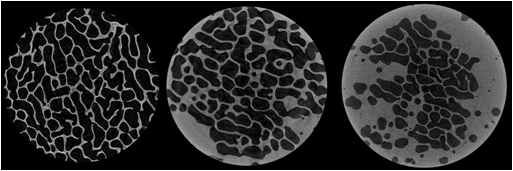

Inoltre, nel Settore di Istomorfometria, Microarchitettura Biomateriali Osso vengono eseguite valutazioni istomorfometriche tridimensionali su morfologia e colonizzazione cellulare di scaffolds, tessuti biologici mineralizzati, vascolarizzazione di organi e tessuti utilizzando una microtomografia computerizzata di ultima generazione (SkyScan 1172).

Vengono effettuate analisi per caratterizzare biomateriali, scaffold e dispositivi in fase pre-impianto che all’espianto. In particolare:

- analisi di biomateriali prima dell’impianto per valutarne porosità o caratteristiche meccaniche;

- analisi di impianti metallici, utilizzati di frequente sia in ortopedia che in odontoiatria, in cui è di primaria importanza lo studio della crescita ossea attraverso la rigenerazione e l’osteointegrazione;

- analisi di impianti polimerici o ceramici per la rigenerazione di difetti e perdite di sostanze ossee;

- studio della morfologia dell’osso, estremamente importante perché numerose patologie ne alterano la microarchitettura (osteoporosi e altre patologie o terapie che influenzano il tessuto osseo). Inoltre, dopo l’impianto di un biomateriale è importante non solo valutare quantitativamente la crescita ossea, ma anche la qualità dell’osso rigenerato. Oltre alle analisi istomorfometriche 3D, vengono creati, partendo dalle sezioni micro-CT, modelli tridimensionali virtuali che forniscono visualizzazioni realistiche del campione di grande utilità anche per comprenderne appieno le strutture.

I modelli possono venire utilizzati per creare filmati dell’oggetto analizzato in movimento o come base per prototipi in ingegneria tessutale.